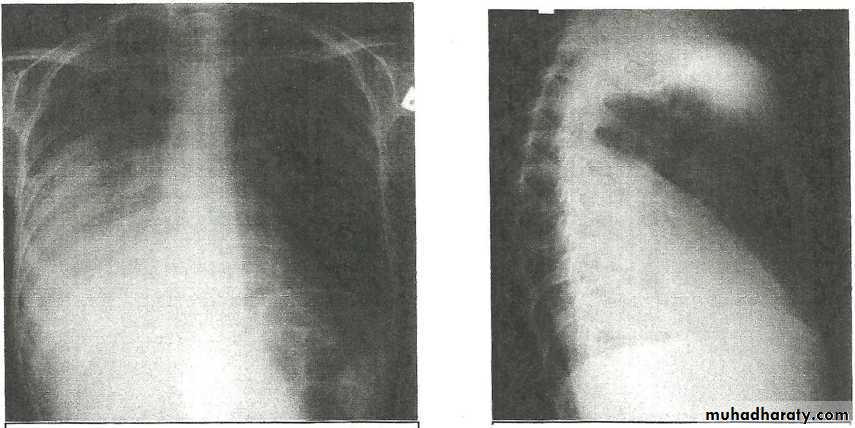

Massive pleural effusion with mediastinal shift to the left.

(A) Chest radiograph(B) CT coronal reconstruction. A massive effusion displaces the mediastinum to the left. CT shows the important pleural effusion together with the enhanced atelectatic left lung.

Note also the depression of the right hemidiaphragm (arrows).